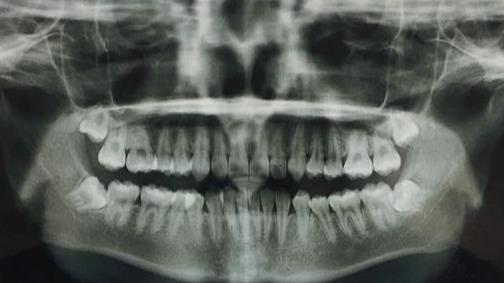

相信许多朋友都有过内部牙龈疼痛的经历。但是去医院检查,却并没有诊断出龋齿或牙周炎等引起牙龈疼痛最常见的病症。结果拍了片才发现,是牙龈内部长了一颗智齿。

这种情况下,尽早拔掉阻生智齿就是免除后顾之忧最好的选择。甚至我们在条件允许的情况下趁早下手,可以提前拔除智齿的牙胚,不让它有萌出和干扰其他牙齿的机会。现在检查智齿都会拍X全景片,片里可以清楚地看到有没有智齿牙胚,如果没有太大风险的(比如牙胚位于下颌神经管内),我们都可以在智齿萌出之前,选择合适的时机进行开窗拔除牙胚,不让它有作乱的机会。